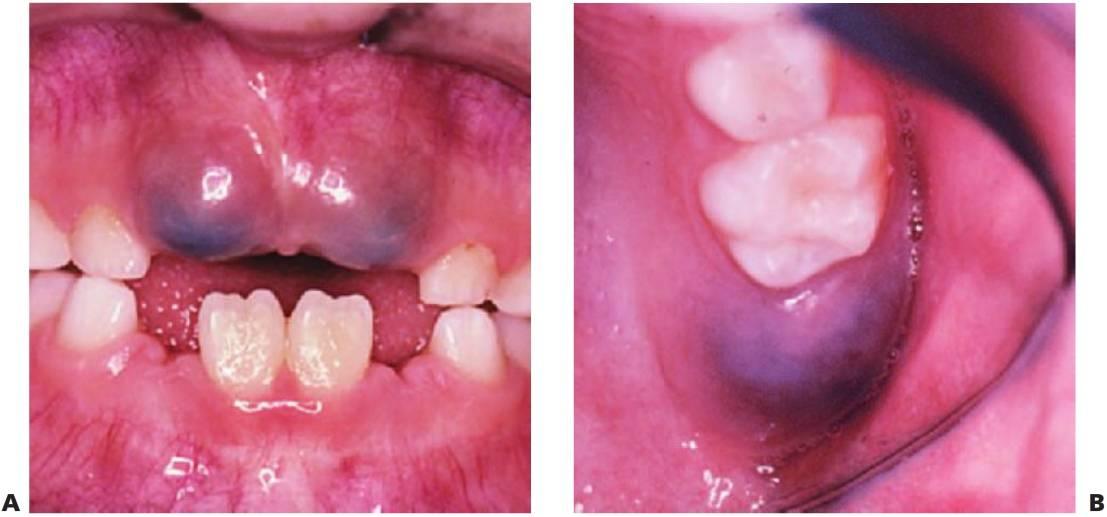

Las infecciones de la fosa canina del maxilar suelen producirse por grampositivos o bacterias anaerobias facultativas (fig. 8.1 A), pero pueden diagnosticarse de forma errónea como una celulitis periorbitaria, que se suele producir por Haemophilus influenzae o Staphylococcus aureus de diseminación hemática. La diseminación posterior puede llevar a una trombosis del seno cavernoso y a un absceso cerebral.

- Drenaje de pus. Si se ha retrasado el diagnóstico del tratamiento adecuado de una infección en la mandíbula y la inflamación ha cruzado la línea media, o bien existe una inflamación en el suelo de la boca, se debe considerar la realización de un drenaje extraoral de entrada-salida (fig. 8.1B, C). Si se eleva un colgajo, se debe eliminar todo el tejido de granulación e irrigar la zona minuciosamente. Los colgajos han de aposicionarse y suturarse sin ejercer mucha tensión con las suturas. Por último, los niños toleran mejor los drenajes flexibles blandos que los tubos corrugados.

Ulceración de Riga-Fedé

Es una ulceración de la superficie ventral de la lengua causada por un traumatismo producido por los movimientos protrusivos y retrusivos continuos sobre los incisivos inferiores (fig. 8.5B). Se consideraba un hallazgo común en los casos de tos ferina; en la actualidad, se suele ver tan sólo en niños con parálisis cerebral.

Esta infección se produce por el virus de Epstein-Barr (VEB) y afecta principalmente a adolescentes mayores y a adultos jóvenes. La enfermedad posee un marcado carácter infeccioso y se manifiesta con malestar, fiebre y faringitis aguda. En los niños pequeños suelen aparecer úlceras y petequias pequeñas en la parte posterior de la faringe y el paladar blando. Otra característica es que se trata de una enfermedad autolimitante (fig. 8.4A).

Varicela

Se trata de un virus altamente contagioso que provoca varicela en individuos jóvenes y herpes zóster en individuos mayores. Existe una fase prodrómica de malestar y fiebre que dura 24 horas y que continúa con erupciones maculares y vesículas. Las lesiones derivadas de la varicela pueden aparecer en la boca (en el 50% de los casos, si bien un pequeño número de las vesículas son orales), así como en zonas mucosas como las conjuntivas, la nariz o el ano. La curación de las lesiones se produce sin complicaciones (fig. 8.4B).